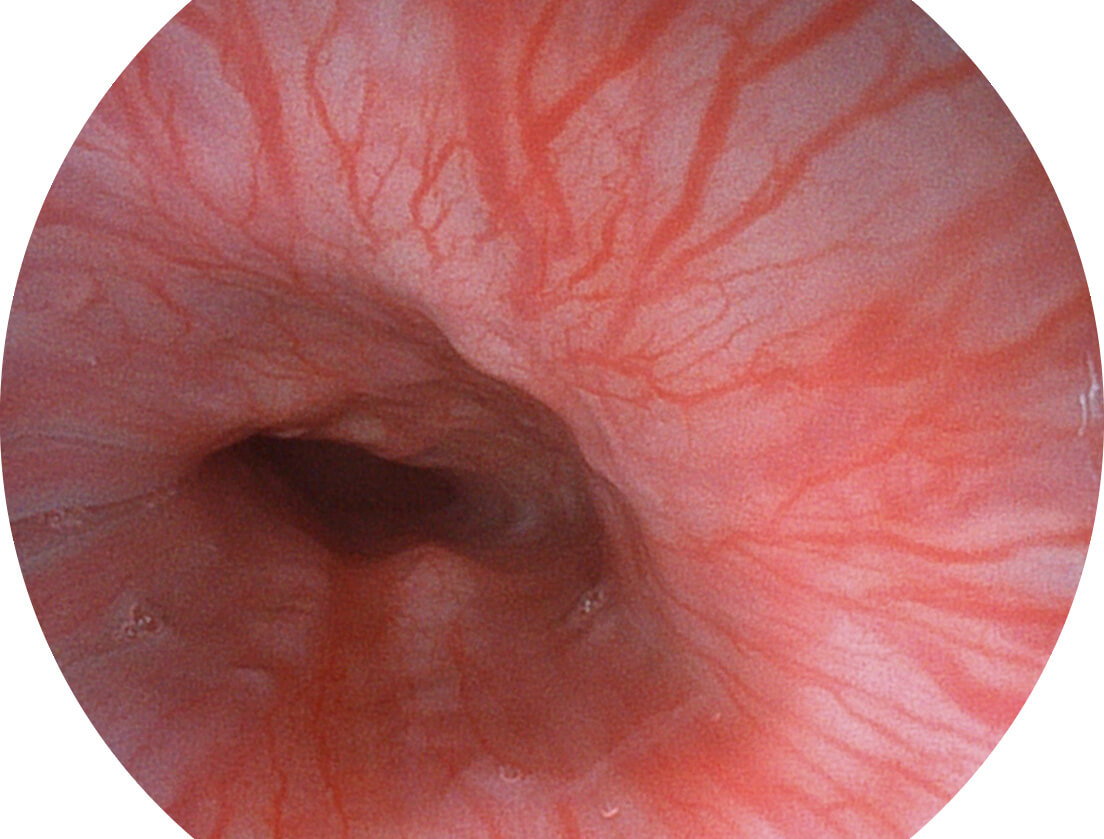

图像具有高亮度、高黏膜血管颜色对比度的特点,且不改变粘液、食物残渣、粪便的基本颜色,可在中远景下进行观察,助力消化道早期疾病的诊断。

• 白光图像 SFI图像

• 白光图像 VIST图像